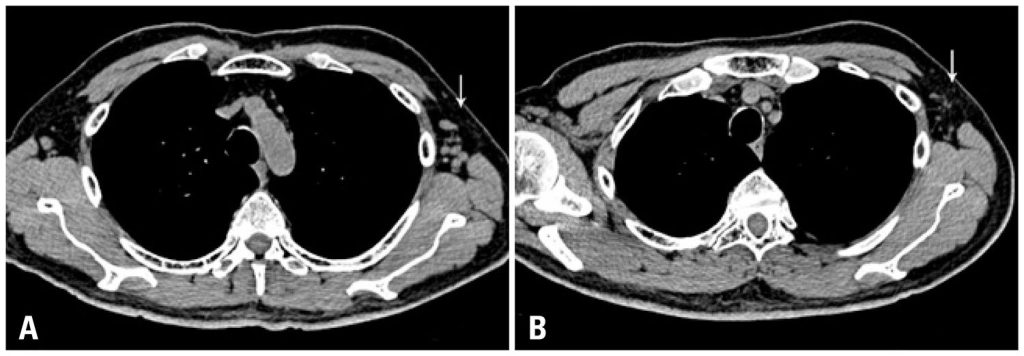

The authors report the case of a 70-year-old male patient with chronic lymphoid leukemia who presented subsequently a papillary carcinoma of the thyroid with metastases to regional lymph nodes. The patient was treated with surgical thyroidectomy with regional and cervical lymph node excision and radioiodine therapy (I-131). The protocolar control scintigraphy 4 days after the radioactive dose showed I-131 uptake in both axillae and even in the inguinal regions. PET/CT showed faint FDG-F-18 uptake in one lymph node of the left axilla. An ultrasound guided fine needle biopsy of this lymph node identified by I-131 SPECT/CT and FDG-F-18 PET/CT revealed lymphoma cells and was negative for thyroid tissue and thyroglobulin content. The sequential blood counts done routinely after radiation treatment showed a marked fall until return to normal values of leucocytes and lymphocytes (absolute and relative), which were still normal in the last control 19 months after the radioiodine administration. Chest computed tomography showed a decrease in size of axillary and para-aortic lymph nodes. By immunohistochemistry, cells of the lymphoid B lineage decreased from 52% before radioiodine therapy to 5% after the procedure. The authors speculate about a possible sodium iodide symporter expression by the cells of this lymphoma, similar to some other non-thyroid tumors, such as breast cancer cells.